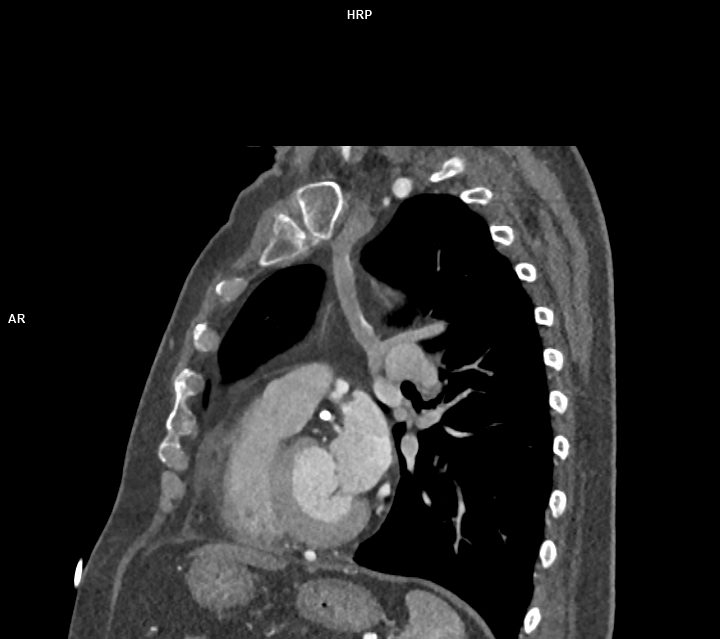

Figura 3: reconstrucție MIP oblică din achiziție CT postcontrast

Discuţie caz nr 47: variantă anatomică de formare a sistemului venos cav inferior cu persistența de venă cavă superioară stângă – există varinate anatomice în care vena cavă superioară stânga este singurul element de drenaj al sângelui de la nivelul extremității cefalice și membrelor superioare. Este important de cunoscut la pacienții ce urmează proceduri interventionale / de cateterizare cardiacă sau la pacienții care au nevoie de cateter venos central.